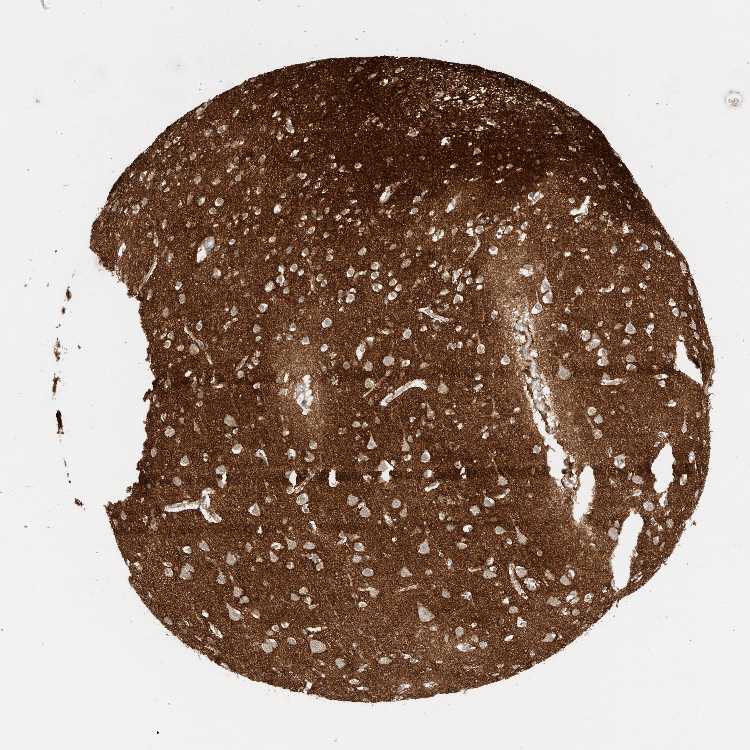

CEREBRAL CORTEX - Antibody stainingi

Antibody staining in the annotated cell types in the current human tissue is reported as not detected, low, medium, or high, based on conventional immunohistochemistry profiling in selected tissues. This score is based on the combination of the staining intensity and fraction of stained cells.

Each image is clickable and will lead to virtual microscopy that enables deeper exploration of all samples and also displays staining intensity scores, fraction scores and subcellular localization as well as patient and tissue information for each sample.

Antibody HPA007865Antibody CAB025862

Endothelial cells Not detectedLow

Glial cells Not detectedMedium

Neuronal cells LowMedium

Neuropil HighHigh